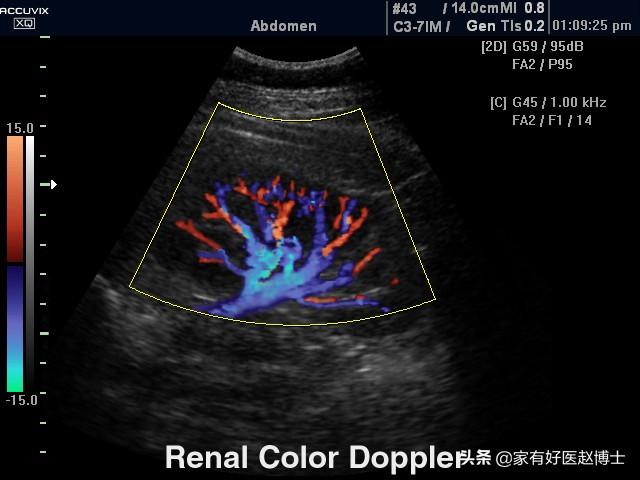

腎臓超音波検査

腎動脈の超音波検査はカラードップラー超音波フローイメージングとも呼ばれ、腎動脈の血流に対する抵抗の指標を評価する。高血圧による腎障害は、腎の葉間動脈の血流に対する抵抗の増加を最初に引き起こすことが示されており、そのため腎動脈超音波検査で評価される腎葉間動脈の血流抵抗指数は、高血圧性腎障害の早期診断にも有用である